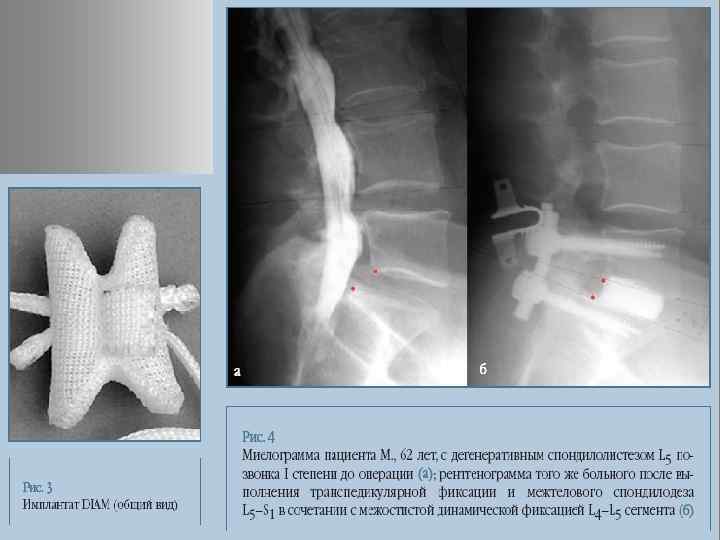

Динамическая система стабилизации

ИМ ПЛ АН ТЫ